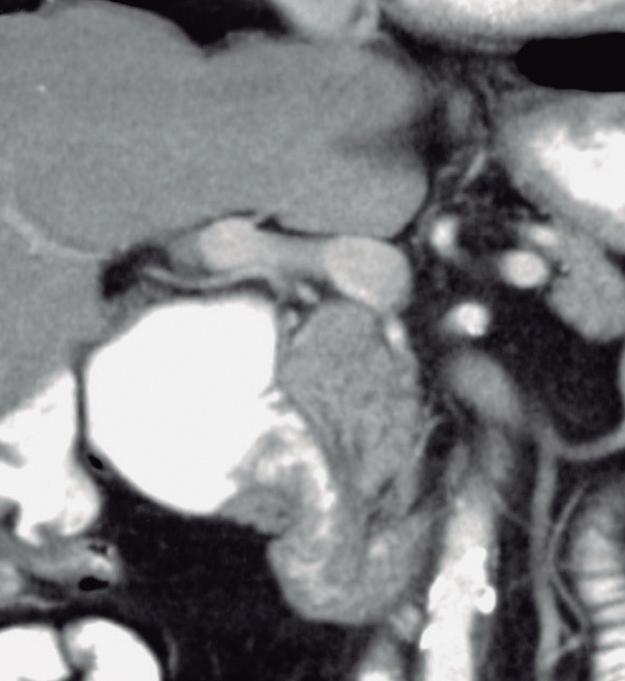

Consiste en una anomalía de la migración del brote pancreático ventral, el cual no rota o lo hace de manera incompleta, resultando en la presencia de tejido glandular pancreático a la derecha del duodeno, rodeando a su 2° porción (Figura 8). Han sido descriptos dos subtipos: el extramural, donde el conducto de Wirsung rodea al duodeno uniéndose al conducto pancreático principal; y el intramural, donde el tejido pancreático se entremezcla con la pared duodenal y sus secreciones drenan directamente a la luz a través de conductos muy pequeños.16

En las imágenes encontramos parénquima pancreático rodeando a la 2° porción duodenal, habitualmente en toda su circunferencia y en ocasiones de manera incompleta. En la colangio-RM es posible visualizar al conducto pancreático a la derecha del duodeno, con un recorrido que se dirige a la ubicación de la papila mayor (Figura 9).17

A) Resonancia magnética secuencia T1 con gadolinio, plano axial. Las flechas señalan el parénquima del páncreas prolongado hacia la derecha “abrazando” a la 2° porción duodenal (cabeza de flecha). B) Resonancia magnética, secuencia T1 con gadolinio, plano axial, corte más caudal al previo. Las flechas nos muestran al páncreas rodeando de manera completa a la 2° porción del duodeno. C) Resonancia magnética, secuencia T2, plano coronal. La flecha señala presencia de parénquima glandular y conducto pancreático a la derecha del duodeno (cabezas de flecha). D) Resonancia magnética, secuencia T2, plano coronal, corte posterior al previo. El páncreas anular y su conducto de drenaje rodean en forma completa al duodeno (cabezas de flecha). E) Colangio-RM. El conducto del páncreas ventral (flechas) hace un giro, rodea al duodeno (cabeza de flecha) y se une al conducto pancreático principal para drenar en la papila mayor. F) Colangio-RM. La imagen magnificada muestra con mayor detalle el recorrido del conducto de Wirsung en el contexto de un páncreas anular.